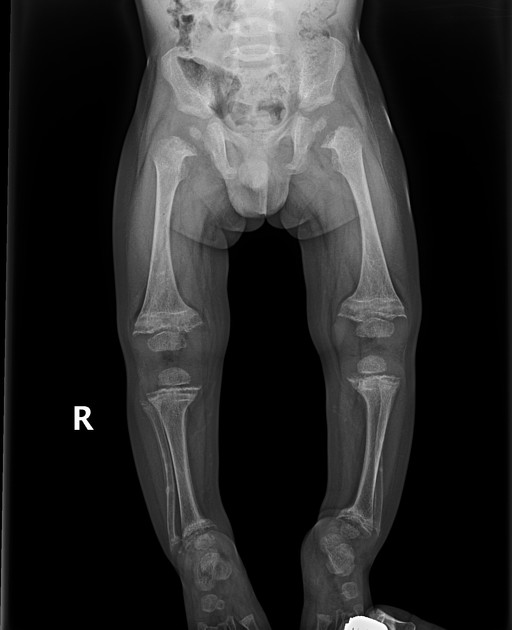

What is the most common symptom of rickets?

Bowed legs.

What is the best imaging modality to diagnose rickets?

Plain X-rays.

What is seen on X-rays of a rickets patient?

Bowed legs and widened wrists due to metaphyseal cupping.